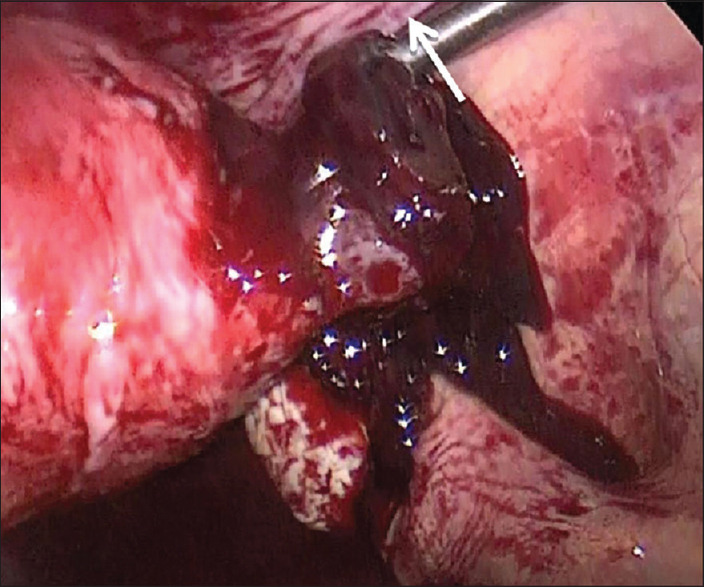

Regarding a Cornual Pregnancy after Salpingectomy for Isthmic Pregnancy.

峡型妊娠输卵管切除术后子宫角妊娠。